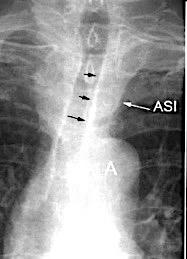

Líneas paraespinales formando un “paréntesis” por encima del diafragma. El signo señala el origen “intratorácico” de la lesión.

Conrad A et al. Pott’s disease associated with large and multiple abscesses in a 30-year-old migrant from Chad. BMJ Case Rep 2018

(lesiones toracoabdominales) La divergencia de las líneas paraespinales apunta a lesión toracoabdominal, que desde el tórax desciende y penetra en el abdomen.

Signo del “iceberg” positivo en Tb vertebral

Afectación por vía hematógena. Región dorsolumbar más frecuente. Afectación inicial: irregularidad de los platillos vertebrales, disminución del disco intervertebral con esclerosis ósea adyacente. Kim. Radiographics.2001